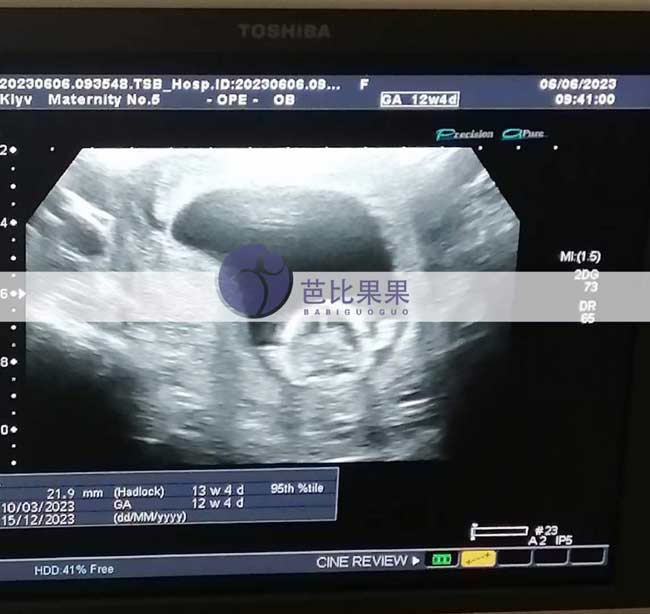

L先生家的乌克兰试管妈妈来做孕12周B超检查报告胎稳了

L先生家的乌克兰试管妈妈来做孕12周B超检查,胎儿发育得很好,已经胎稳了。试管妈妈的身体也很健康,脸色红润。